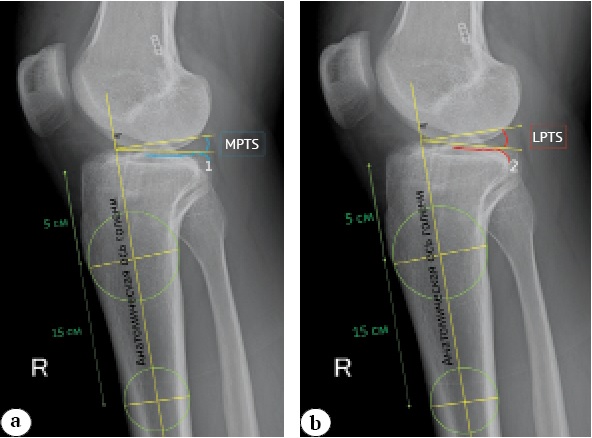

Technique for measuring MPTS and LPTS on X-rays

Measurements were conducted using the Radiant DICOM Viewer, v. 2021.2 (Medixant, Poland). To minimize measurement errors, two senior physicians from the department independently performed measurements, and the average value of all measurements was determined.

The posterior tibial slope was determined on lateral-view knee radiographs relative to the anatomical axis of the tibia. This was determined by inscribing two circles on the proximal part of the shin, 5 and 15 cm distal to the joint surface, and drawing a line connecting their centers. The surface of the medial (blue line) and lateral (red line) tibial plateaus was determined (Fig. 1). The angle between the tangent and the central axis of the tibia was measured. MPTS and LPTS were determined using the formula:

MPTS and LPTS = 90° - the angle between the anatomical axis of the tibia and the tangent drawn along each plateau.